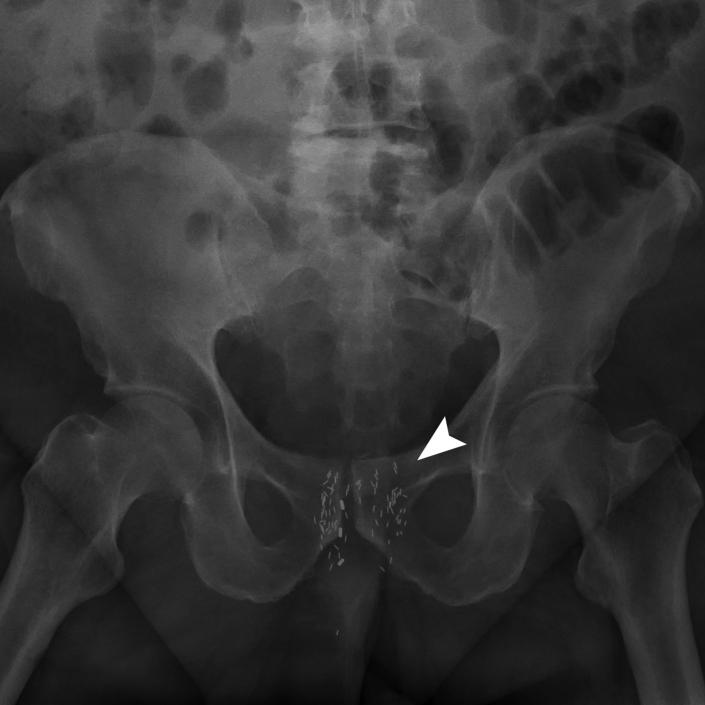

Brachytherapy consists of placing radioactive sources into or adjacent to tumors, to deliver conformal radiation treatment. The technique is used for treatment of primary malignancies and for salvage in recurrent disease. Permanent prostate brachytherapy seeds are small metal implants containing radioactive sources of I-125, Pd-103, or Cs-131 encased in a titanium shell. They can embolize through the venous system to the lungs or heart and subsequently be detected by cardiovascular computed tomography. Cardiovascular imagers should be aware of the appearance of migrated seeds, as their presence in the chest is generally benign, so that unnecessary worry and testing are avoided. We report a case of a patient who underwent brachytherapy for prostate cancer and developed a therapeutic seeds embolus to the right ventricle.

近距离放射治疗是将放射源放置在肿瘤内部或附近,以进行适形放射治疗。该技术用于原发性恶性肿瘤的治疗以及复发性疾病的挽救治疗。永久性前列腺近距离放射治疗种子是小的金属植入物,包含封装在钛壳中的碘-125、钯-103或铯-131放射源。它们可通过静脉系统栓塞至肺或心脏,随后可通过心血管计算机断层扫描检测到。心血管成像人员应了解迁移种子的表现,因为它们在胸部的存在通常是良性的,从而避免不必要的担忧和检查。我们报告一例接受前列腺癌近距离放射治疗并发生治疗性种子栓子至右心室的患者。